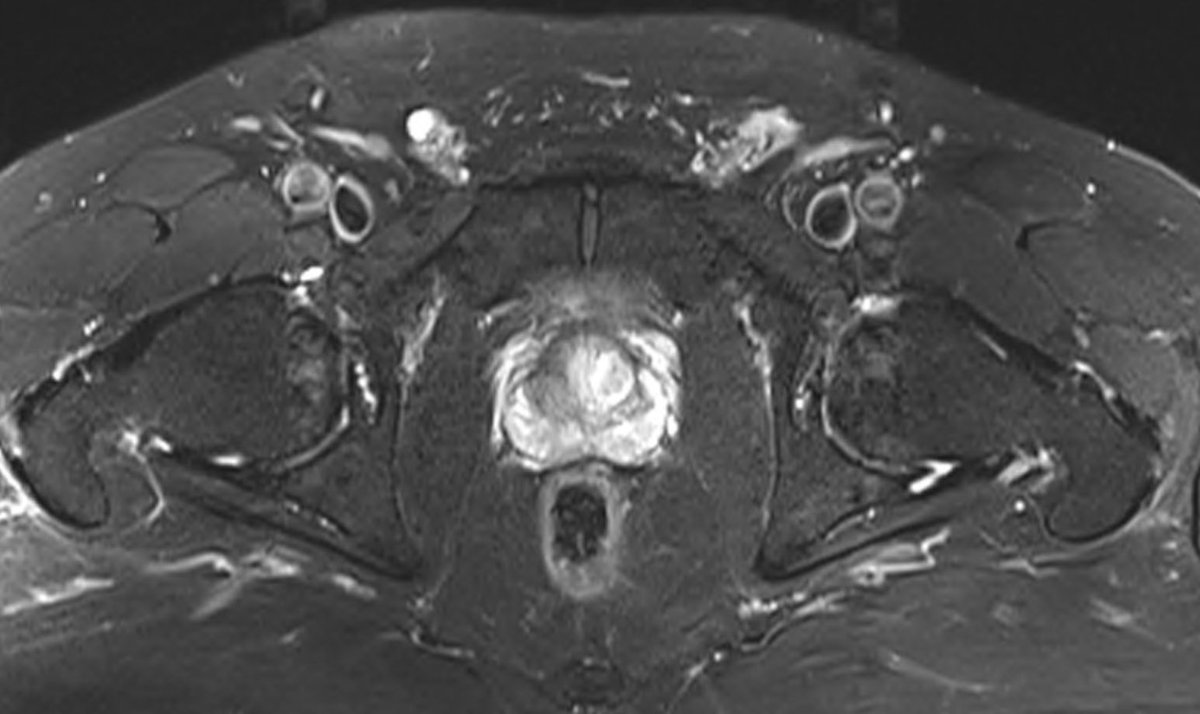

6. request mri LSp - spondylolisthesis L5/S1 and facet hypertrophy causing nerve root compression (bilateral!), associated disc Modic 1 changes

7. So - is it nerve root? Facet? Somatic discogenic pain - relevance of Modic 1 changes? Is it the small hernia? Occult inguinal soft tissue / external ring driver - often underestimated on mri - with genitofemoral nerve component? Is it the hip joint (prob not).

8. lots of potential abnormalities (which could be found in a pain free population). imaging is valid at this point, but it has maybe created more questions than answers. But at least rules out âred flagâ.